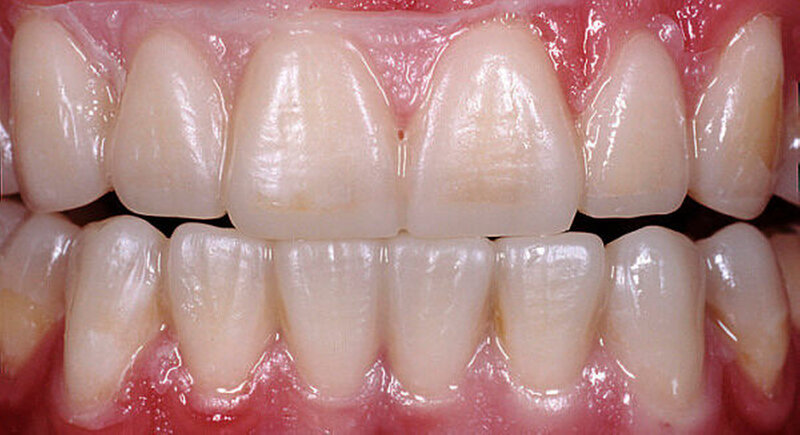

Nach einer klinischen Funktionsanalyse (Abbildungen 1 und 2) werden Situationsmodelle hergestellt und diese anhand einer arbiträren Scharnierachsbestimmung und eines Zentrikregistrats im Artikulator montiert. Die für die spätere Versorgung funktionell und ästhetisch ideale Vertikaldimension wird durch ein analytisches Wax-up eingestellt (Abbildung 3). Dieses wird in eine diagnostische Schablone (Tiefziehfolie) für eine „ästhetische Evaluierung“ durch den Zahnarzt und den Patienten überführt. Dazu kann die Schablone mit niedrigviskösem Komposit gefüllt und reversibel auf die mit flüssiger Vaseline isolierten Zähne gesetzt werden. Findet dieser Restaurationsvorschlag die Zustimmung des Patienten, wird im zahntechnischen Labor eine in der Höhe und in der Bisslage dem Wax-up entsprechende Repositionsschiene mit Front-Eckzahn-Führung angefertigt. Diese Schiene sollte circa drei Monate möglichst permanent getragen werden. Diese „funktionelle Evaluierung“ dient dazu zu prüfen, ob der Patient die neue Bisslage beschwerdefrei toleriert [Edelhoff et al., 2013; Harper, 2000; Rivera-Morales et al.,1992].

Wird die Bisslage vom Patienten beschwerdefrei akzeptiert, kann die Übertragung der Situation entweder direkt in vollkeramische Restaurationen oder zunächst in CAD/CAM-gefräste, langzeitprovisorische Repositions-Veneers oder -Onlays aus Hochleistungs- polymer – meist PMMA-Material – erfolgen (Abbildung 4). Für die Konstruktion können die Datensätze der Wax-up-Modelle verwendet werden. Die Table Tops werden gewöhnlich mittels Adhäsivtechnik auf natürlichen Zähnen und Kunststofffüllungen befestigt, können allerdings auch bei entsprechender Vorbehandlung (intra-orales Anstrahlen) auf metallischen und keramischen Restaurationsoberflächen eingesetzt werden [Bertolotti et al., 1994]. Da die neue Bisssituation nun permanent inkorporiert ist, können sich die neuronalen Bewegungsmuster besser adaptieren. Um künftig funktionelle Beschwerden nach definitiver Rekonstruktion der vertikalen Kieferrelation möglichst auszuschließen, sollte diese semipermanente Phase für etwa sechs bis zwölf Monate beibehalten werden.